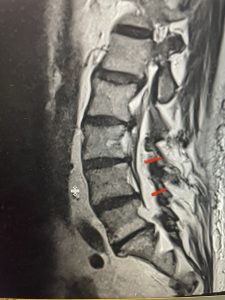

This 57 year-old male had a long history of low back pain and left lower extremity pain and numbness. The patient had failed conservative treatment of physical therapy and epidurals. MRI revealed tight left L2-3 and L3-4 lateral recess stenosis as well as significant right L4-5 facet arthropathy and right lateral recess stenosis as well as a grade 1 L4-5 spondylolisthesis

(Fig 2) Sagittal T2-weighted lumbar MRI demonstrating (arrow) tight lateral recess stenosis

It was felt that the patient should undergo surgical decompression and fusion at L4-5 given his spondylolisthesis. Post operatively he had an uneventful course and he had relief of his leg pain.